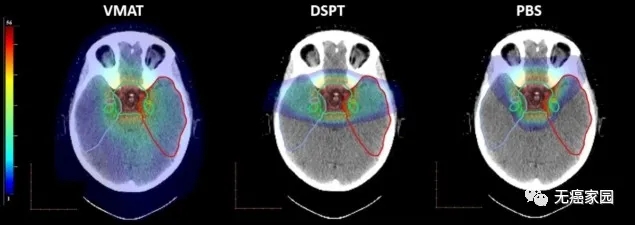

(从左到右)VMAT、DSPT 和 PBS 的剂量分布。目标体积(绿色)以及颞叶和子结构的轮廓。对于记忆功能起关键作用的一个大脑区域是海马体。该研究发现,即使使用DSPT,41%的左侧海马也接受了低剂量的辐射,但是通过PBS治疗可以避免海马体受到辐射,因而记忆功能未受到影响。

在意大利米兰举行的欧洲放射治疗与肿瘤学会(Estro)38会议上公布了一项质子治疗研究结果。科学家发现,笔束扫描质子治疗(PBS)最有可能使大脑区域对记忆仍起重要作用,也就是说笔束质子放疗治疗脑瘤时,对儿童大脑的记忆功能没有影响。

丹麦研究人员对10名接受过大脑肿瘤治疗的儿童进行了详细研究。该团队使用CT(计算机断层扫描)和MRI(磁共振成像)扫描来确定儿童大脑中的30个结构受到不同形式放射治疗的影响程度,结果发现笔束质子治疗对儿童大脑记忆功能区的不良影响最小。